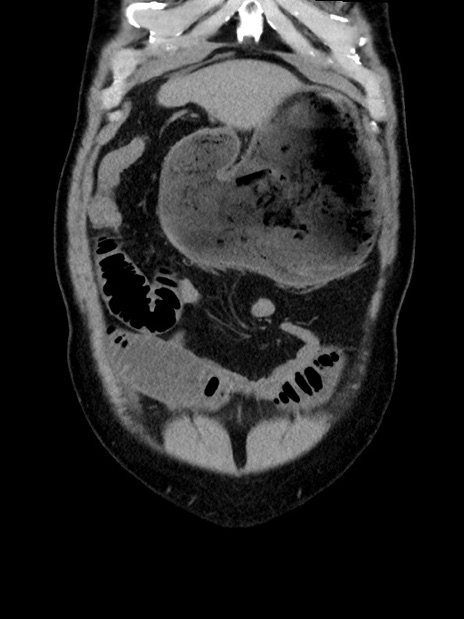

横断像

【症例】70歳代 男性

【主訴】腹部膨満、嘔吐

【現病歴】昨日より腹部膨満感出現。本日増悪し、仙痛出現。嘔吐あり、受診。

【既往歴】糖尿病、胆摘後

【身体所見】BP 149/80mmHg、HR 74/min、BT 35.9℃、腹部:膨満、軟、圧痛なし。腸雑音減弱あり。上腹部正中切開瘢痕あり。

【データ】WBC 13500、CRP 1.72